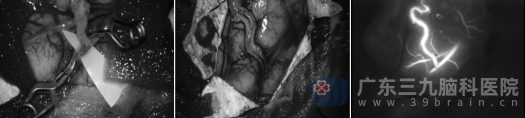

针对陈女士右侧大脑半球严重的缺血状态,外十科团队决定为其施行“右侧颞浅动脉-大脑中动脉搭桥术+右侧颢肌敷贴术”。这一手术被誉为神经外科的“明珠-血运重建”,需要在显微镜下将几根头发丝般粗细的血管精准吻合。

医生在高清显微镜下聚精会神“绣花”数小时,才将细小血管吻合成功。手术过程非常顺利。术后复查CTA显示:右侧颞浅动脉血管伸入颅内与右侧大脑中动脉远段吻合良好,桥血管显示清晰,局部皮层可见多发细小血管影,这意味着新建立的血液循环通路已经成功“接管”了部分供血任务。